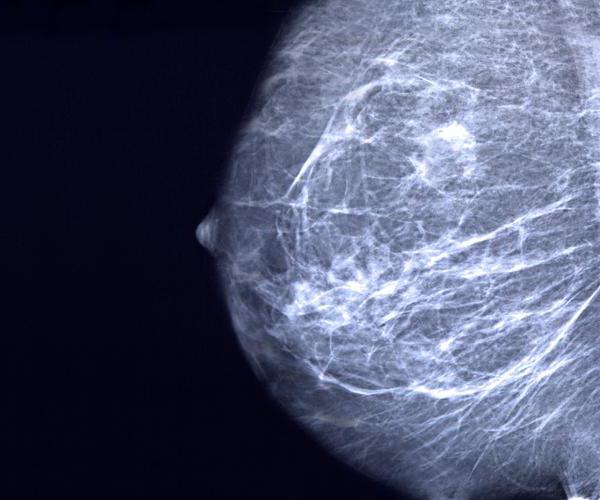

Медицинское средство "Мамоклам" (цена, отзывы, инструкция представлены в статье) является доступным для большинства пациентов. Он используется в медицине для лечения в основном мастопатии определенного характера. Данное нарушение работы организма свойственно женщинам после дисбаланса уровня гормонов. Это может быть связано с резким прерыванием лактации, прерыванием беременности или воспалительным заболеванием половой системы. В любом случае терапию необходимо начинать как можно скорее, поскольку запущенные формы мастопатии легко трансформируются в злокачественные опухоли, бороться с которыми в дальнейшем становится еще сложнее.